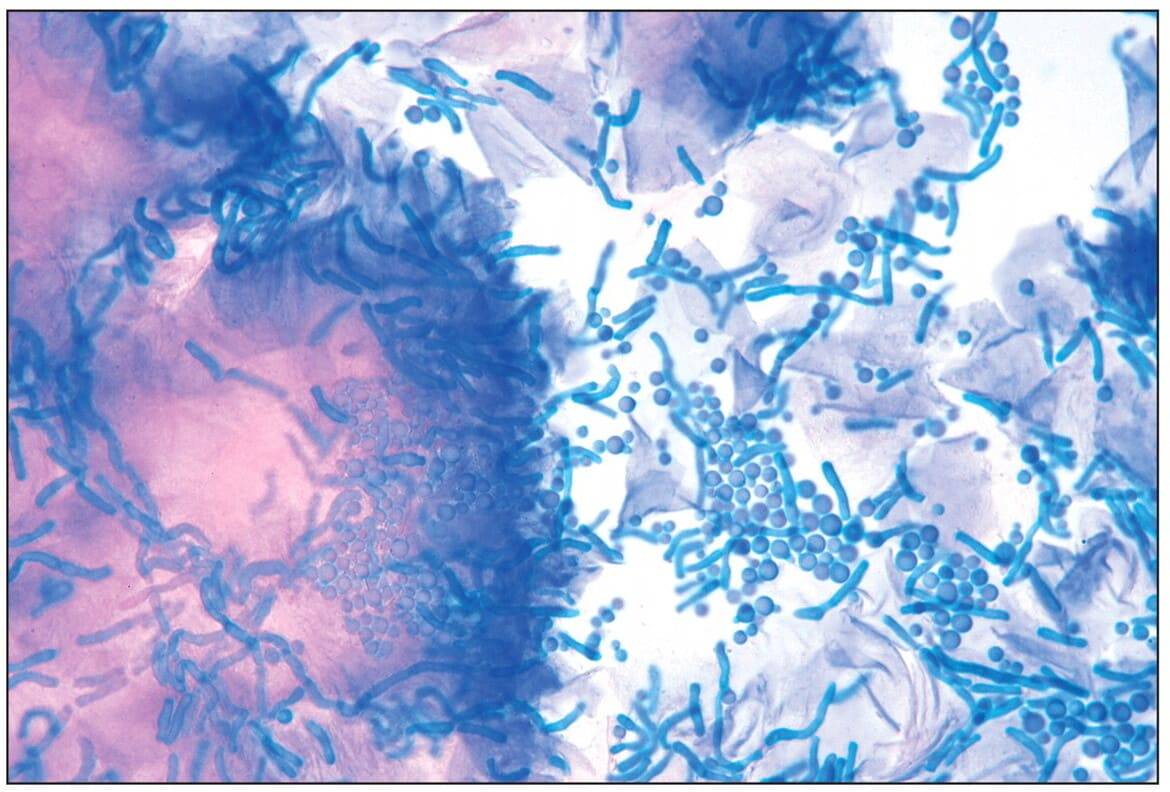

Диагноз педикулеза подтверждает обнаружение гнид в волосах и взрослых особей. Гниды часто путают с перхотью

Важное отличие в том, что яйца вшей не отделяются от волос при легком прикосновении, требуется приложить усилие. При раздавливании гнид слышен щелчок

Гниды – самый явный признак заражения. Именно они выдают присутствие головных кровососов задолго до их непосредственного обнаружения. Выглядя яйца как белые коконы, расположенные на отдельных волосках. Располагаются они чаще всего ближе к корням, но могут находиться и на другом участке.

Пустые коконы еще долгое время остаются на месте крепления и при запущенном педикулезе прическа больного выглядят как посыпанная белой крупой.